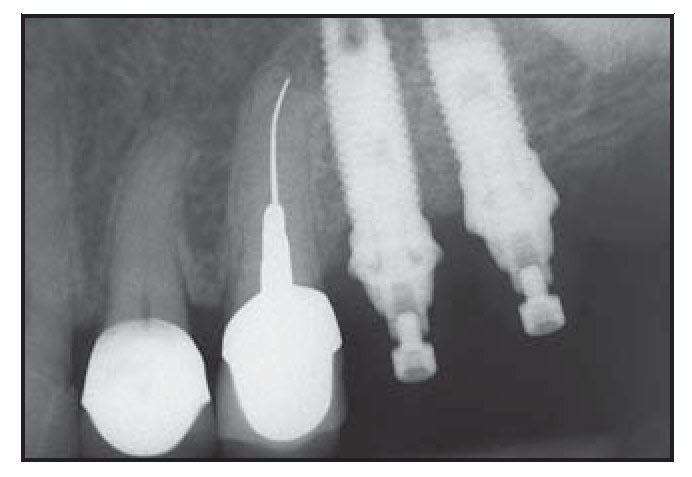

En los 5 o 6 pacientes en los que se retrasó la colocación de los implantes se colocaron 1 o 2 minitornillos para soportar la membrana de barrera (figura 1a). La selección del tipo de minitornillo (mecanizado o revestido por hidroxiapatita) fue aleatoria. Se prepararon las osteotomías para los minitornillos con una fresa de 1,0 mm de diámetro utilizando una solución salina estéril para su irrigación. Se modificó la longitud del tornillo a utilizar de forma que el extremo apical del tornillo se pudo fijar al hueso residual en la base del defecto sin invadir estructuras vitales. La cabeza del tornillo no se extendió más allá de la altura del hueso adyacente al defecto. La longitud se ajustó reduciendo el extremo apical del minitornillo mediante una fresa y posteriormente cada minitornillo se insertó en el lecho receptor con un contra-ángulo. Se utilizaron sondas periodontales para medir la distancia desde la base del defecto óseo hasta la superficie más coronal del minitornillo y se registró la altura del minitornillo expuesto antes de realizar el injerto óseo vertical. En los dos pacientes en los que se realizó de forma simultánea el injerto y la colocación de los implantes, éstos se colocaron después de degranular por completo todos los restos de tejido blando e irrigar con solución salina estéril.

Figura 1 Paciente 1.

Figura 1a Reabsorción pronunciada del hueso del maxilar superior posterior izquierdo del paciente. Obsérvense las roscas expuestas del minitornillo.

Figura 1d (izquierda) Radiografía de carga inicial.

Figura 1e (derecha) La radiografía 9 años después de la carga muestra los niveles estables de hueso marginal.